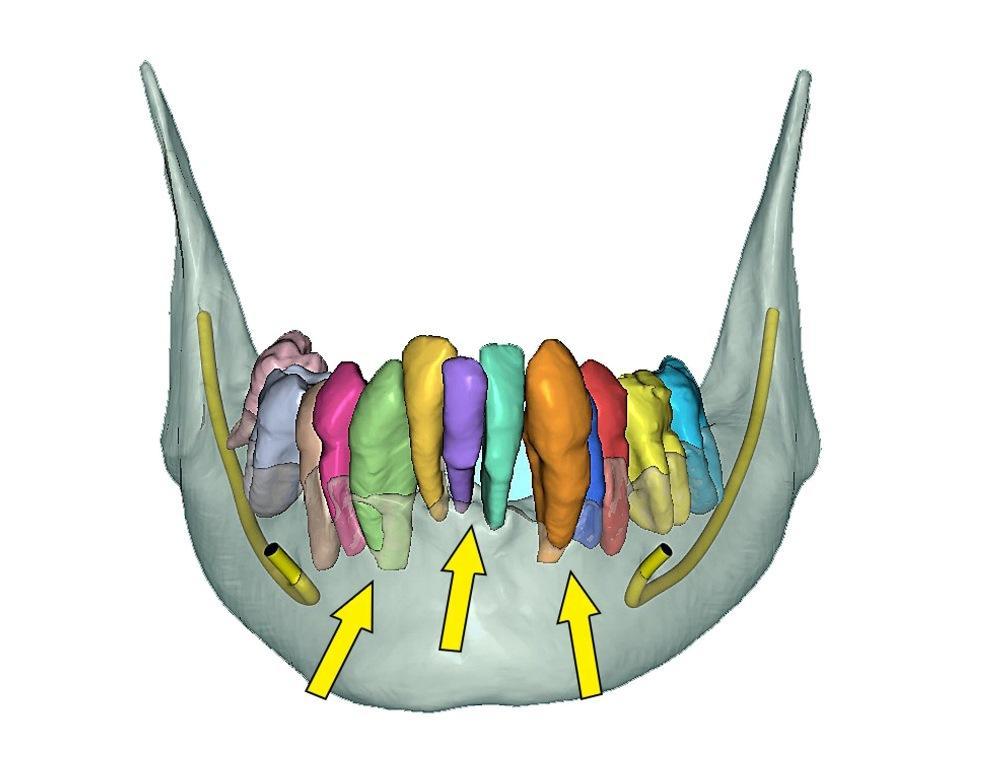

После удаления зубов и репозиции кости операция на нижней челюсти проводилась по аналогичному хирургическому протоколу с использованием костной хирургической направляющей. Развитая сегментация костей и зубов свидетельствовала о серьезной потере костной ткани почти до верхушки многих корней нижней челюсти (фото 13a). Используя выборочную прозрачность, можно было тщательно оценить корни и кость (фото 13b). Объемная 3D-реконструкция, имитирующая кость после удаления, позволила получить уникальное представление об анатомии кости нижней челюсти (фото 14a) и помогла окончательно определить местоположение каждого имплантата (фото 14b).

Фото 13a: Полностью сегментированный нижняя челюсть и зубы.

Фото 13b: Выборочная прозрачность: видны корни, двусторонние ментальные нервы и нижний альвеолярный нерв (желтые стрелки указывают на верхушки корней, показывая степень потери костной ткани).